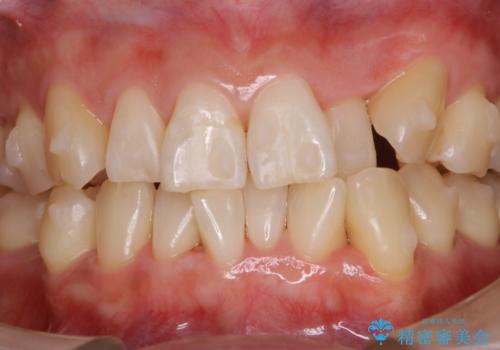

インビザラインでのマウスピース矯正中に歯を白くしたい

- インビザラインでのマウスピース矯正中に、歯の黄ばみが気になるため綺麗に白くしたいとのことでした。PMTC60分コースを行いました。

PMTC(保険外治療)は、毎日の歯磨きで落としきれない汚れや、コーヒ、紅茶・タバコのヤニなどの着色も除去します。目には見えない歯と歯の間・歯肉の境目・インビザライン中はアタッチメント周囲などに残っているプラーク(歯垢)もしっかり取り除きます。PMTCでは専門的な機械や材料を使用して、徹底的に汚れを除去するため、虫歯・歯周病・口臭予防などにつながります。

またPMTCを行うことで、ご自身本来の歯の色になり自然な明るさになります。